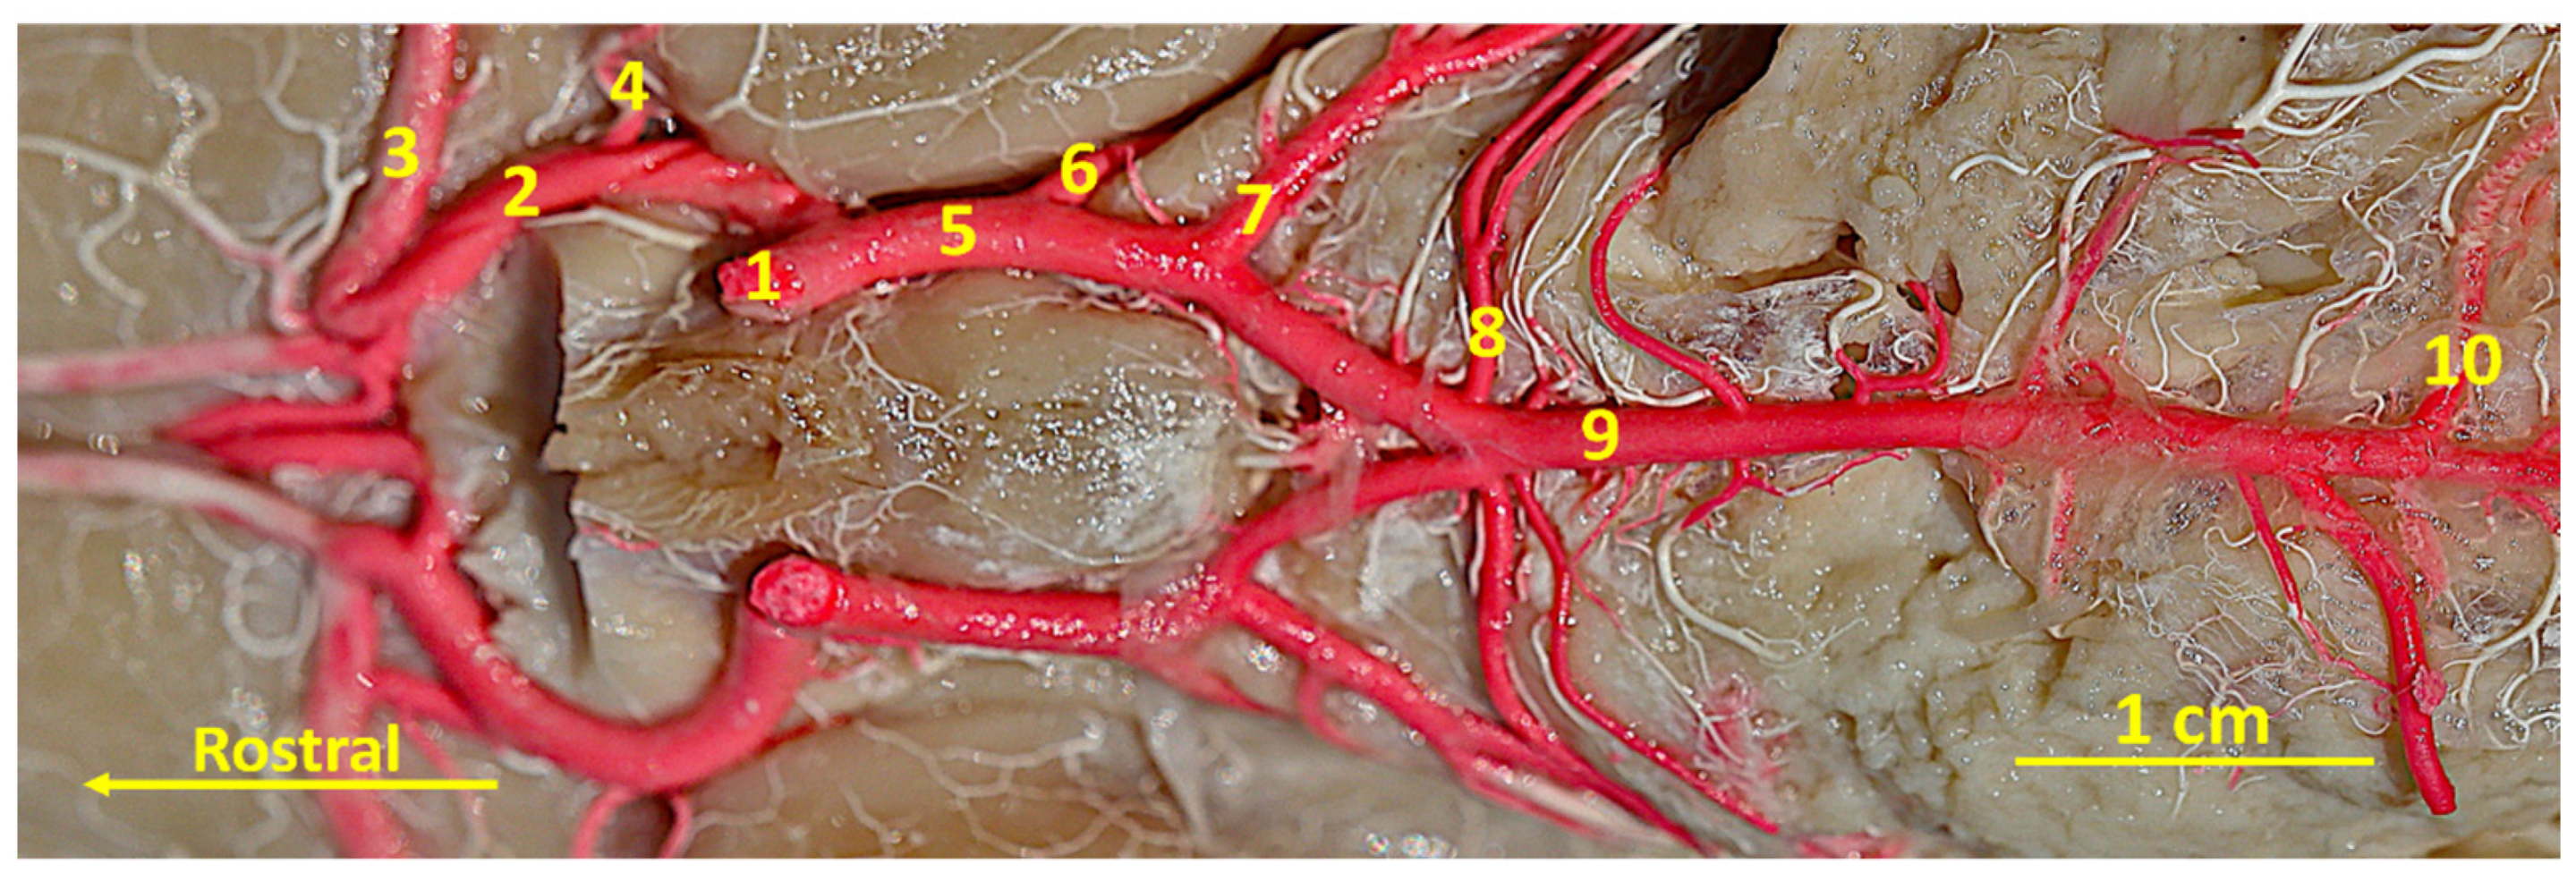

3. Results